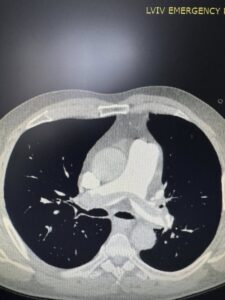

Вчора ввечері до нашої клініки потрапив чоловік із блискавичним розвитком тромбоемболії легеневої артерії — стану, який у багатьох випадках забирає життя за лічені хвилини. Другий – військовий, який лікувався в хірургічному відділенні з приводу мінно-вибухової травми та сьогодні отримав важку масивну тромбоемболію легеневої артерії.

Команда лікарів Першого територіального медичного об’єднання міста Львова прийняла рішення в обох випадках провести ендоваскулярну тромбаспірацію — сучасне, малоінвазивне втручання, що дозволяє механічно видалити тромб із легеневої артерії без відкритої операції. Саме цю методику освоїли нещодавно на конгресі інтервенційних радіологів в Барселоні!

Під рентгенконтролем через судини катетером ми дісталися тромбів й видалили їх спеціальною системою аспірації.